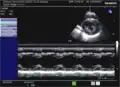

- Mit dem M-Mode werden von parasternal die Aortenklappe, die Funktion des linken Ventrikels und die Mitralklappe untersucht.

M-Mode durch den linken Ventrikel